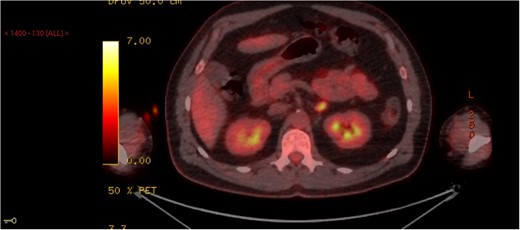

A whole body NM FDG PET-CT was performed. This reported high metabolic activity in his left adrenal gland with an increase in size—highly suspicious for a malignancy (Fig. 1). He was referred to the endocrine surgeons for consideration of excision of his adrenal mass and also to the thoracic surgeons for a lung wedge biopsy which confirmed KS. We performed a laparoscopic left adrenalectomy following his wedge biopsy. Intra-operatively, the adrenal gland was mobilized from adjacent structures without difficulty and there no evidence of local invasion or peritoneal disease. He was discharged the following day and had an unremarkable recovery.

PET scan demonstrating a left adrenal lesion with high metabolic activity.